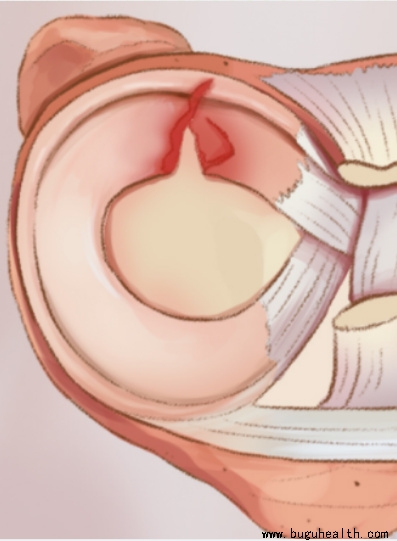

- 半月板(meniscus)是膝关节中的纤维软骨,是保护膝盖防止退化最重要的组织,它可以吸收运动时的震荡,传递下肢的力量,润滑和稳定膝盖关节。 .....

- 半月板损伤,是一种很常见的膝关节损伤,经常会有朋友尤其是那些热爱运动的朋友们,会问到类似的问题,询问自己的半月板损伤到底严不严重,要不要手术,损伤后还能运动吗?今天就带大家了解半月板.....

- 半月板损伤,是指半月板因外伤或退行性病变而出现损伤,是膝关节中最常见的损伤。半月板损伤患者可出现关节疼痛、肿胀、膝关节活动受限、关节交锁、弹响等症状。半月板损伤要采用医疗康复和自我康复结合的方式,一般恢复较慢,时间较长;只要采用恰当的方法,半月板损伤是可以预防的。.....